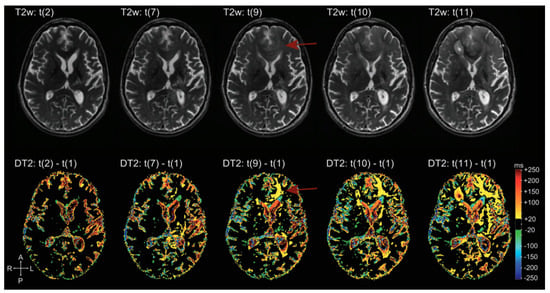

9. Quantitative MRI

- Ellingson, B.M.; Cloughesy, T.F.; Lai, A.; Nghiemphu, P.L.; Lalezari, S.; Zaw, T.; Motevalibashinaeini, K.; Mischel, P.S.; Pope, W.B. Quantification of edema reduction using differential quantitative T2 (DQT2) relaxometry mapping in recurrent glioblastoma treated with bevacizumab. J. Neuro-Oncol. 2012, 106, 111–119. [Google Scholar] [CrossRef] [PubMed]

- Ellingson, B.M.; Kim, H.J.; Woodworth, D.C.; Pope, W.B.; Cloughesy, J.N.; Harris, R.J.; Lai, A.; Nghiemphu, P.L.; Cloughesy, T.F. Recurrent glioblastoma treated with bevacizumab: Contrast-enhanced T1-weighted subtraction maps improve tumor delineation and aid prediction of survival in a multicenter clinical trial. Radiology 2014, 271, 200–210. [Google Scholar] [CrossRef] [PubMed]

- Hattingen, E.; Jurcoane, A.; Daneshvar, K.; Pilatus, U.; Mittelbronn, M.; Steinbach, J.P.; Bähr, O. Quantitative T2 mapping of recurrent glioblastoma under bevacizumab improves monitoring for non-enhancing tumor progression and predicts overall survival. Neuro-Oncology 2013, 15, 1395–1404. [Google Scholar] [CrossRef] [PubMed]